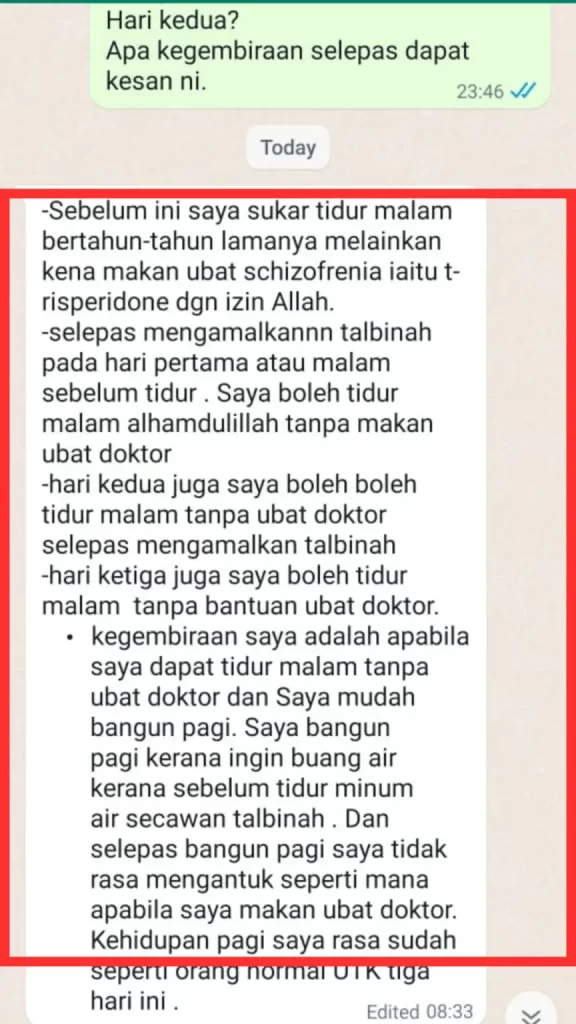

"Boleh tidur malam tanpa makan ubat hospital, ada schizo, dan mudah bangun"

Lihat salah seorang pengguna kami yang anxiety dan depression.

Disangkakan sihir sampai kelar tangan dan kerap maki hamun, tetapi alhamdulillah dengan ikhtiar Talbinah semakin baik seawal 3 hari.